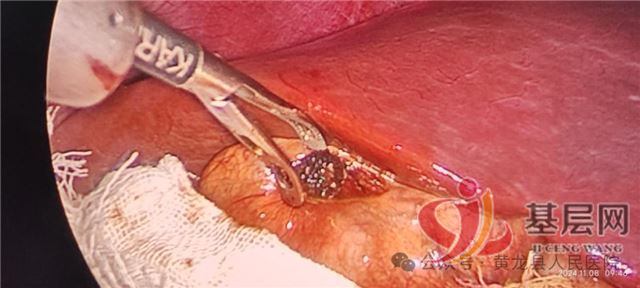

中国基层网讯(通讯员:郝雪茹)近日,黄龙县人民医院外科腔镜手术再传佳讯,在唐都医院肝胆外科帮扶专家贺小军带领下,成功为一名29岁胆囊结石患者顺利完成我院首例腹腔镜下保胆取石术,在最大程度减少创伤的基础上为患者保留了完整胆囊及其功能,患者术后恢复良好。手术的成功实施填补了县域内腔镜技术在胆囊结石疾病治疗领域的空白,同时标志着黄龙县人民医院外科微创治疗再上新台阶。

为尽早减轻患者疼痛,让患者得到精准高效救治,方继荣主任迅速组织全科医务人员讨论治疗方案,并邀请唐都医院肝胆外科帮扶专家贺小军参加会诊,经过多次、详细、周密的研究讨论,结合患者自身意愿,最终制定出详细周密的手术方案,告知患者及家属治疗方案,取得同意后,在手麻科配合下,顺利为患者实施“腹腔镜下保胆取石术”。手术顺利,达到了术前预期效果,术后患者入住外科无痛病房,在外科医务人员的精心治疗及优质护理下,恢复良好,术后1天即可下地活动、进少量易消化食物,目前已康复出院。患者及家属对手术和住院感受非常满意,为表达对贺小军专家和外科全体医护人员的感谢,出院后特意制作一面写有“医生仁心尽心尽责、护士有爱堪比南丁”字样的鲜红锦旗送到外科病区。

相比传统开腹手术,腹腔镜下保胆取石具有手术视野清晰、操作时间短、创伤小、术中出血少、疼痛轻及恢复快等诸多优点,且其既保留了胆囊及其功能,又取净结石,减轻了临床症状,充分展示了腹腔镜下保胆取石术的优势。